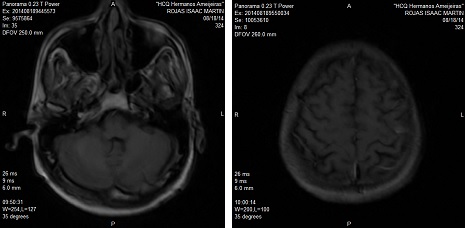

RNM de cráneo endovenoso (EV), 22 de agosto de 2014: se realizan cortes axiales FLAIR y sagitales, apreciándose en la región fronto-parietal izquierda alta una lesión que mide aproximadamente 15 x 12 mm (imagen 3).

IMAGEN 3. RNM de cráneo EV: 22 de agosto de 2014